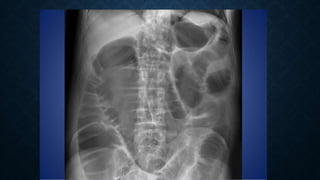

This document provides an overview of x-rays for medical students, covering topics such as ensuring x-rays are well-aligned, exposure levels, common artifacts and anatomical features, abdominal x-ray positions and views, and specialized x-rays including barium swallows, enemas, and tests to examine the esophagus, small bowel, biliary tree, and kidneys.